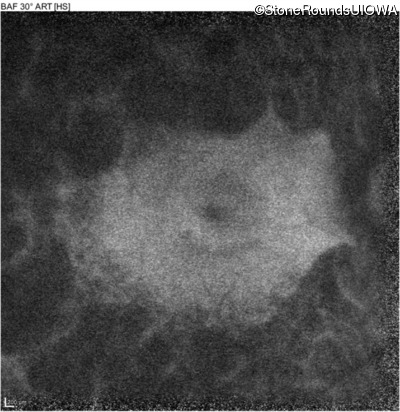

Visit at age: 51 years

Optical Coherence Tomography - Right - 20/50

Exemplar / OCT Stack